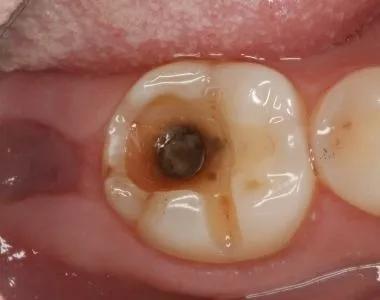

第二阶段:牙齿出现小黑洞,说明引起中度蛀牙,细菌腐蚀来到牙本质,伴随着牙齿敏感,黑色腐败物质其实就是细菌的产物,这时候还可以再补牙;

第三阶段:牙齿超过一半烂掉,说明已经重度蛀牙,细菌伤及牙髓牙神经,还伴随着剧烈疼痛,牙神经病变这时得根管治疗处理,挽救伤痕累累的牙齿。